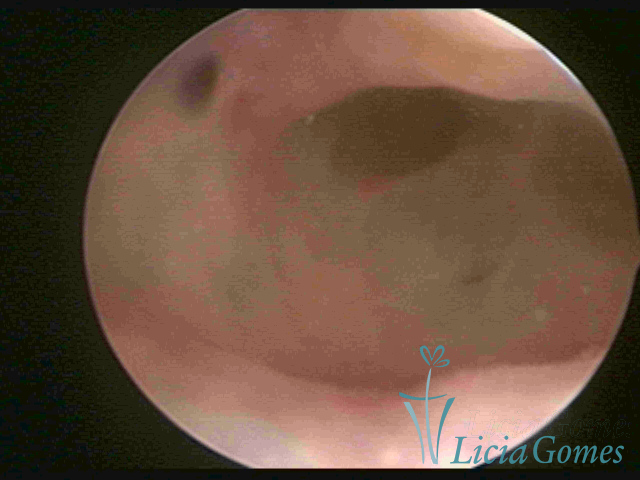

ADENOMYOSIS

The presence of endometrial tissue on the muscular layer of the uterus.

Video hysteroscopy allows diagnosing the lesions next to the superficial myometrial layers next to the endometrium, allowing the view of in situ, purplish, or chocolate brown lesions.